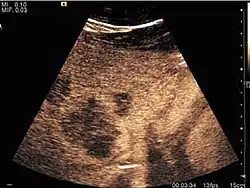

HCC appearance on 2D ultrasound is that of a solid tumor, with imprecise delineation, with heterogeneous structure, uni- or multilocular (encephaloid form). An "infiltrative" type is also described which is difficult to discriminate from liver nodular reconstruction in cirrhosis. Typically HCC invades liver vessels, primarily the portal veins but also the hepatic veins . Doppler examination detects a high speed arterial flow and low impedance index (correlated with described changes in tumor angiogenesis). The spatial distribution of the vessels is irregular, disordered. CEUS examination shows hyperenhancement of the lesion during the arterial phase. During the portal venous phase there is a specific "wash out" of ultrasound contrast agent (UCA) and the tumor appears hypoechoic during the late phase. Poorly differentiated tumors may have a stronger wash out leading to an isoechoic appearance to the liver parenchyma during portal venous phase. This appearance was found in approx. 30% of cases. The described changes have diagnostic value in liver nodules larger than 2 cm.

Ultrasound is useful in HCC detection, stadialization and assessing therapeutic efficacy. In terms of staging related to therapy effectiveness, the Barcelona classification is used which identifies five HCC stages. Curative therapy is indicated in early stages, which include very early stage (single nodule <2 cm), curable by surgical resection (survival 50-70% five years after surgical resection) and early stage (single nodule of 2–5 cm, or up to 3 nodules <3 cm) which can be treated by radiofrequency ablation (RFA) and liver transplantation. Intermediate stage (polinodular, without portal invasion) and advanced stage (N1, M1, with portal invasion) undergo palliative therapies (TACE and sorafenib systemic therapy) and in the end stage only symptomatic therapy applies.